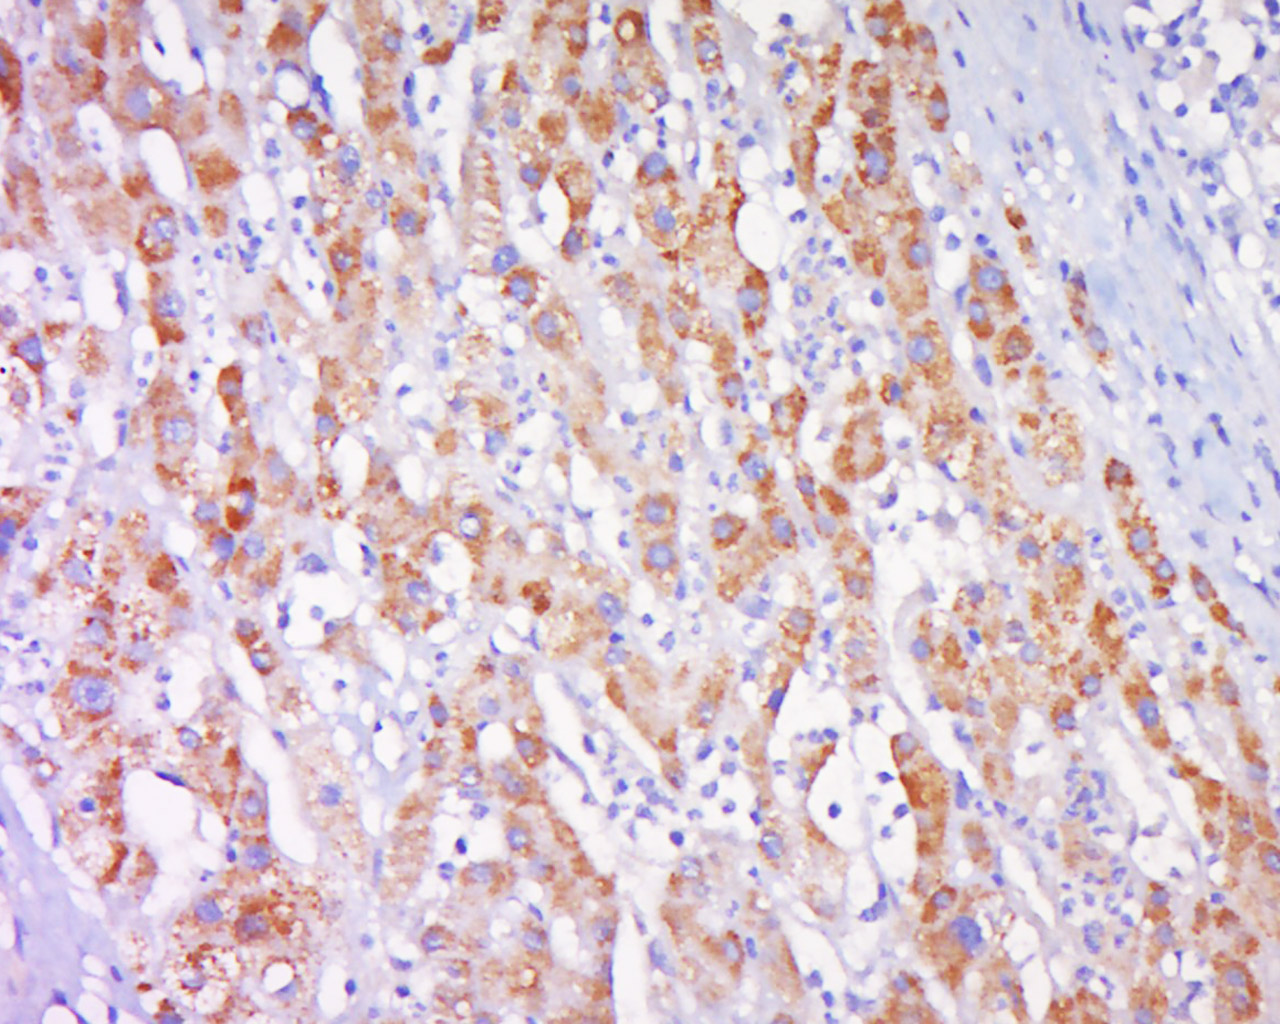

Antigen retrieval: citrate buffer ( 0.01M, pH 6.0 ), Boiling bathing for 15min; Block endogenous peroxidase by 3% Hydrogen peroxide for 30min; Blocking buffer (normal goat serum,C-0005) at 37℃ for 20 min;

Incubation: Anti-CPNE1 Polyclonal Antibody, Unconjugated(bs-14024R) 1:500, overnight at 4°C, followed by conjugation to the secondary antibody(SP-0023) and DAB(C-0010) staining